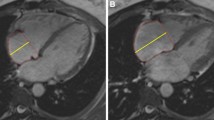

By logistic regression, an RV GFI cut off value of 43% predicted incidence of CAO with a sensitivity of 76% and specificity of 83% (AUC 0.83). Based on this dichotomy, patients with RV GFI ≤ 43% demonstrated decreased freedom from CAO during median follow up of 2.7 years (p < 0.001) (Fig. 2).

Patients were dichotomized using logistic regression threshold RV GFI of 43% (AUC 83%, 76% Sensitivity, 83% Specificity). Kaplan–Meier curve demonstrating difference in probability of freedom from composite adverse outcome (CAO: death, lung transplant, Potts shunt, or SQ/IV prostacyclin initiation) based on RV GFI ≥ 43% (blue line) and < 43% (red line) over 1000 days (median follow-up time 710 days). Dashed lines represent 95% confidence intervals (p < 0.0001)